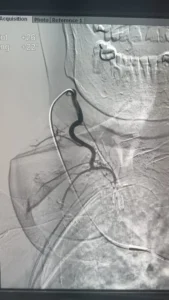

فى إنجاز طبى غير مسبوق داخل مصر، بل و على مستوى الشرق الأوسط، أعلن الدكتور محمود عبد العزيز غلاب – استشارى الأشعة التداخلية – عن نجاحه فى إجراء أول حالة من نوعها فى الأسكندرية لعلاج تضخم الغدة الدرقية عن طريق القسطرة الشريانية، و هو أسلوب حديث تم نقله من اليابان بعد تدريبه فى واحدة من أرقى الجامعات اليابانية المتخصصة فى مجال الأشعة التداخلية.

تعد هذه الحالة الأولى من نوعها التى يتم فيها الدخول عبر القسطرة الشريانية إلى الشرايين المغذية للغدة الدرقية في الإسكندرية.

المريضة، و هى سيدة تبلغ من العمر 81 عامًا، كانت تعانى من تضخم شديد بالغدة الدرقية تسبب فى ضغط على القصبة الهوائية، مع تعدد النتوءات داخل الغدة، إلى جانب معاناتها من أمراض بالقلب حالت دون إمكانية خضوعها لأى جراحة. و بعد رفض حالتها من قِبل أكثر من استشارى جراحة نظراً لخطورة التدخل الجراحى، كان الحل الوحيد هو اللجوء إلى الأشعة التداخلية.

و بسبب كبر حجم الغدة و تعدد النتوءات فيها، لم يكن التردد الحرارى هو الخيار الأمثل، و عليه و بالتنسيق مع الدكتور محمد جلال الغاوى استشاري الغدد الصماء. فقد قام الدكتور محمود غلاب أسلوبًا بالتدخل عبر الحقن بالقسطرة الشريانية، و هو ما مكّن من غلق الشرايين المغذية للنتوءات و بالتالى تقليص حجمهم و تحسين الأعراض بشكل ملحوظ.